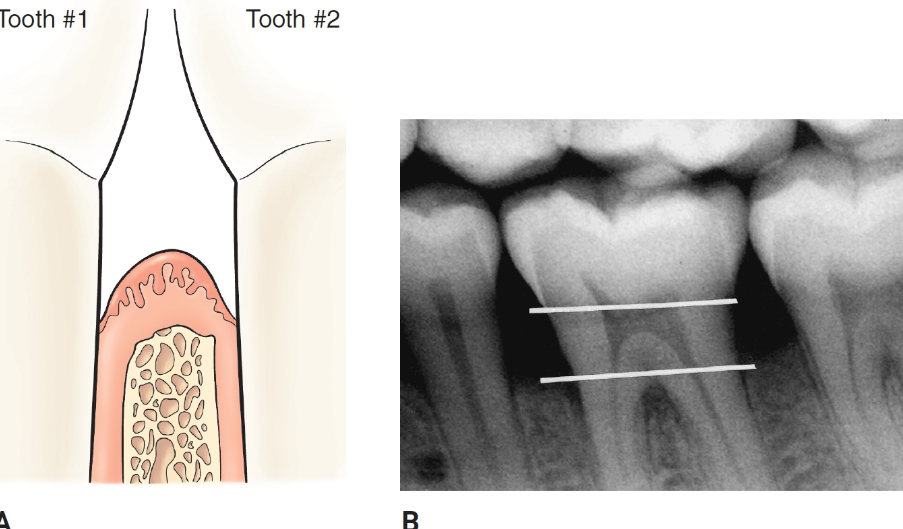

suprabony pocket

base of the pocket is coronal to the crest of the alveolar bone

horizontal bone loss

infrabony pocket

base of the pocket is apical to the crest of the bone

vertical or angular bone loss

in health and gingivitis, the crest of the alveolar bone is located approximately ____ to the CEJ

2-3 mm apical